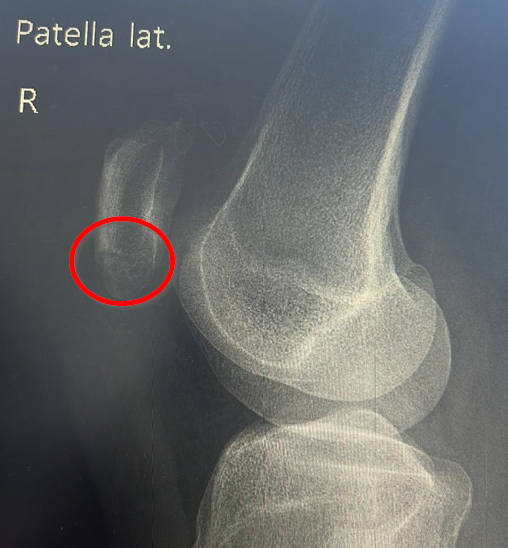

Diese Woche Freitag steht der heiß ersehnte Termin beim Orthopäden an. Das (hoffentlich) letzte Mal röntgen. Wenn ich dort das Okay bekomme, kann es endlich wieder mit dem Laufen und dem Muskelaufbau des rechten Beins los gehen. Momentan ist der Oberschenkelmuskel noch immer eher ein schwabbeliges Etwas und ich freue mich schon darauf, diesen in das zu verwandeln, was er einmal war. Ich bin sehr gespannt, wie der Einstieg ins Laufen klappen wird und wie schnell ich meine Ausdauer wiederaufbauen kann. Ihr werdet es hier auf jeden Fall erfahren!